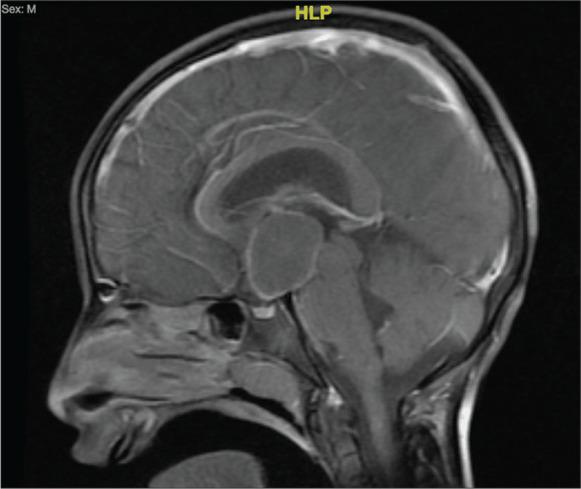

CASE DESCRIPTION

We report two cases from our neurosurgical unit complicated by postoperative cerebrospinal fluid infection caused by that posed a therapeutic challenge.

我们报告了来自我们神经外科病房的两例病例,这两例病例术后并发由[该菌属]引起的脑脊液感染,带来了治疗挑战。